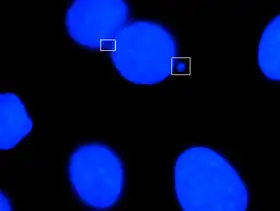

Micronuclei primarily result from acentric chromosome fragments or lagging whole chromosomes that are not included in the daughter nuclei produced by mitosis because they fail to correctly attach to the spindle during the segregation of chromosomes in anaphase. These full chromosomes or chromatid fragments are eventually enclosed by a nuclear membranes and are structurally similar to conventional nuclei, albeit smaller in size. This small nucleus is referred to as a micronucleus. The formation of micronuclei can only be observed in cells undergoing nuclear division and can be clearly seen using cytochalasin B to block cytokinesis to produce a binucleated cells.[2]

One study, which used Giemsa stain to stain nuclear material, established the following criteria for identifying micronuclei:

1) diameter less than 1/3 of the primary nucleus,

2) non-retractility (excludes small stain particles),

3) color the same as or lighter than the main nucleus (excludes large stain particles),

4) location within 3 or 4 nuclear diameters of the main nucleus without touching it, and

5) no more than two associated with one primary nucleus (3 or more micronuclei are likely polymorphs or prorubicytes with nuclear fragments).[6]